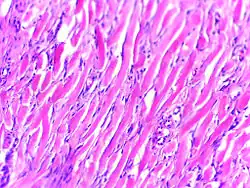

Micrograph of keloid. Thick, hyalinised collagen fibres are characteristic of this aberrant healing process. H&E stain.

Histologically, keloids are fibrotic tumors characterized by a collection of atypical fibroblasts with excessive deposition of extracellular matrix components, especially collagen, fibronectin, elastin, and proteoglycans. Generally, they contain relatively acellular centers and thick, abundant collagen bundles that form nodules in the deep dermal portion of the lesion. Keloids present a therapeutic challenge that must be addressed, as these lesions can cause significant pain, pruritus (itching), and physical disfigurement. They may not improve in appearance over time and can limit mobility if located over a joint.[16]